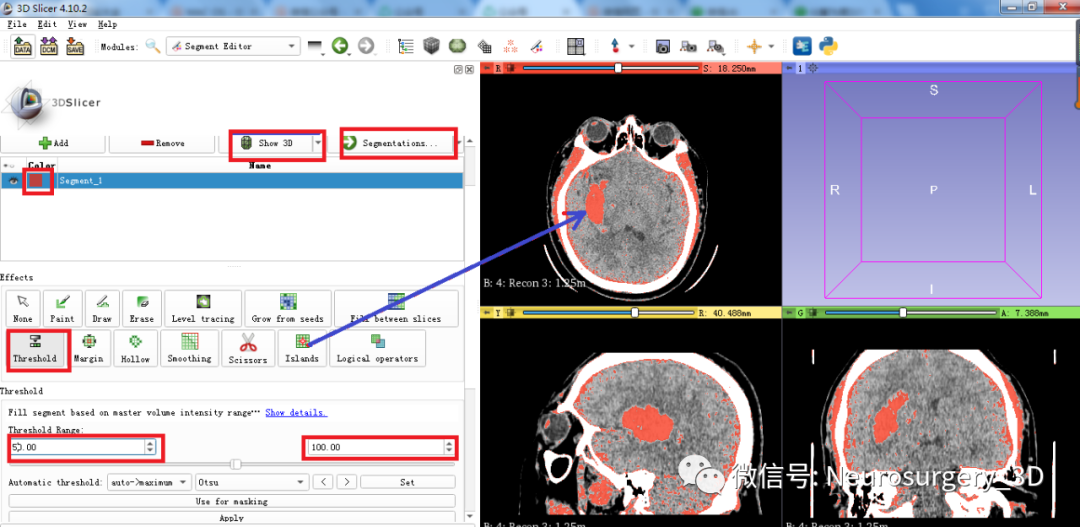

4、应用阈值分割法三维重建血肿

5、利用segmentations分割工具生成血肿Models模型